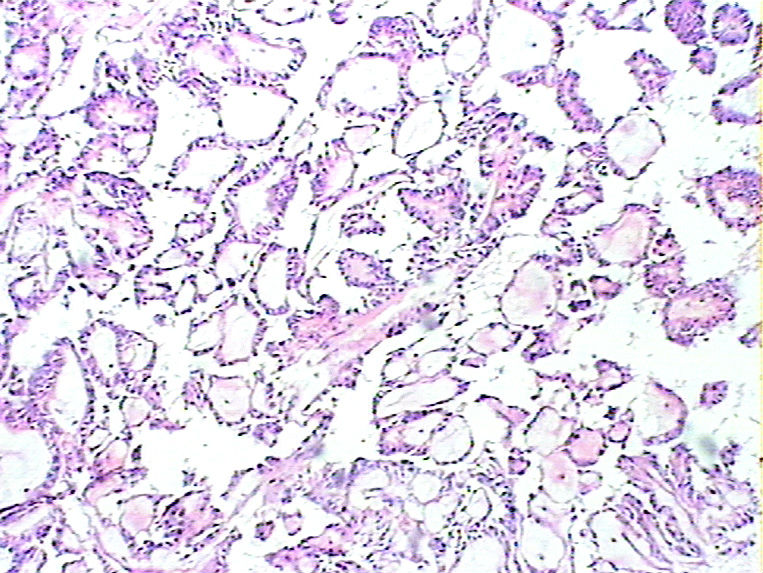

女48 骶尾部皮下见一结节状肿物,,9*6*4cm,切面实性,分叶状,灰白灰红灰黄色,质软。

• 骶尾部肿瘤图1

图1

• 骶尾部肿瘤图2

图2

粘液性室管膜瘤

粘液乳头状室管膜瘤,

是粘液乳头状室管膜瘤,但是楼主提供相关病史、临床资料不能少

会诊粘液乳头状室管膜瘤

骶尾部可以有原发的室管膜瘤,并不一定是转移的

HE切片质量有待提高,但是这个部位,这种乳头状机构,诊断粘液样乳头状室管膜瘤没有问题。